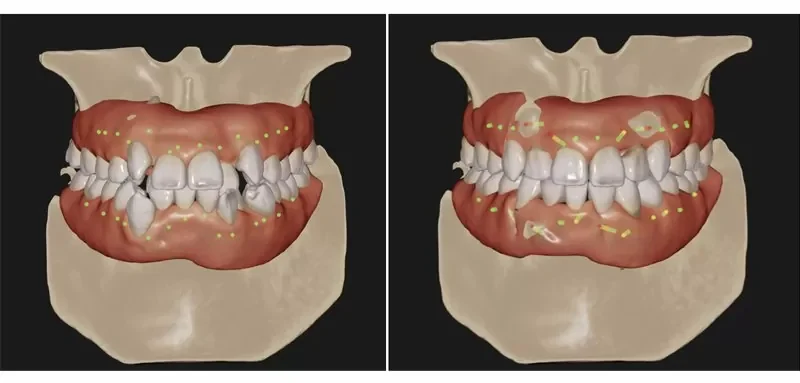

また、無料カウンセリング時には3D光学スキャナー「iTero(アイテロ)」による簡易シミュレーションを行います。短時間でお口の中をスキャンし、現在の歯並びをデジタル化。矯正後の歯並びもシミュレーションできるため、治療後のイメージを具体的に持て、不安の軽減につながります。

AI技術搭載の口腔内スキャナー「iTero」

当院が導入する光学式3Dスキャナー「iTero(アイテロ)」は、AIがスキャンデータを瞬時に解析し、矯正後の歯並びをリアルタイムでシミュレーション表示します。AIが歯の動きや治療計画を緻密に設計します。これにより、患者様は治療の具体的な仕上がりをその場でイメージでき、不安を軽減しながら治療を進められます。

デジタルシミュレーション

デジタルシミュレーションを用いることで、抜歯・非抜歯で治療をおこなった場合や、部分矯正・全顎矯正といった治療範囲、さらに装置の種類まで想定したシミュレーションを行うことができます。